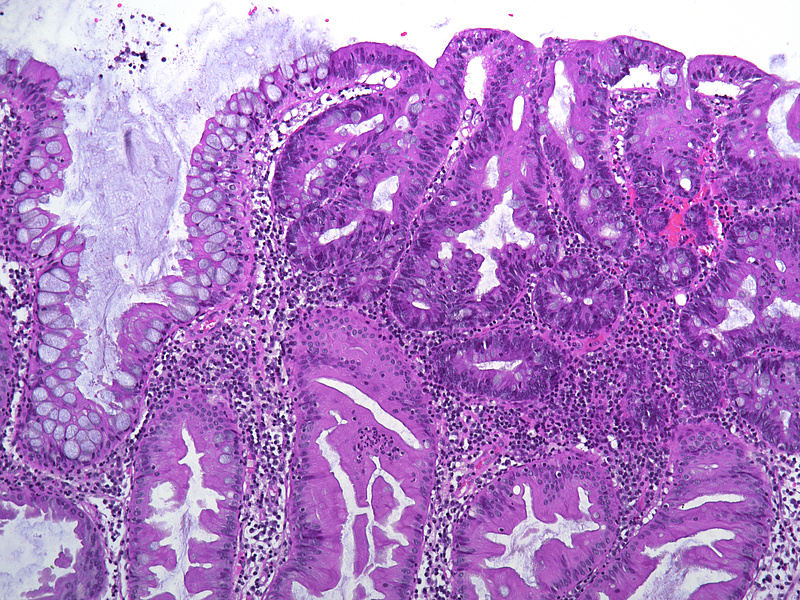

Ascending colon polyp in a 79-year-old male.

Unclassified serrated adenoma.

The ascending colon polyp is a serrated polyp characterized by a combination of two morphological patterns which are sessile serrated lesion (SSL) and traditional serrated adenoma (TSA). The former is formed by architecturally distorted serrated crypts with deep serrations, basal crypt dilatation and lateral growth along the muscularis mucosae (Panels A-B). Some foci of stromal proliferation resembling perineural cells are also seen within this component (Panel C). The TSA component has typical slit-like serrations, lined by tall columnar cells with intensely eosinophilic cytoplasm and pencillate nuclei (Panels D-E). Abrupt transition to dysplastic mucosa and glands are present, where the glands display more complex and crowded architecture with little intervening lamina propria (Panel F). The dysplastic cells show features of adenomatous dysplasia characterized by columnar cells with enlarged hyperchromatic nuclei, pseudostratification and reduced goblet cells (Panel G). In some areas, the cells display high grade cytology with more rounded nuclei and loss of polarity. MLH1 immunostaining was preserved in both the non-dysplastic and dysplastic glands with higher intense staining seen in the latter (Panel H).

The variable morphological features that is present in this polyp makes it difficult to delineate whether this polyp represents a SSL with dysplasia (SSLD) or TSA with overt (adenomatous) dysplasia. Retained MLH1 staining pattern was also not helpful in this case as it is known that both adenomatous and serrated- type dysplasia in SSL will show preserved MLH1 staining. Therefore, when dealing with such complexity in a polyp, it is best to classify such polyp as unclassified serrated adenoma (USA).